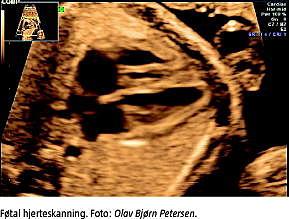

Ved brug af AD til gravide kan man til en vis grad tage højde for eventuelle komplikationer; f.eks. kan udvidet hjerteskanning i forbindelse med de rutinemæssige misdannelsesskanninger anbefales med henblik på at detektere hjertemisdannelser. For eventuelle neonatale komplikationers vedkommende er grundig information til kvinden mht. symptomer, som barnet eventuelt kan få, vigtig. En sammenhængen mellem SSRI og PPHN ses kun sjælden. Tilstanden viser sig umiddelbart efter fødslen, og fordrer primært information til obstetrikere og neonatologer.

TAKSIGELSER: Tak til Olav Bjørn Petersen for ultralydbillede.